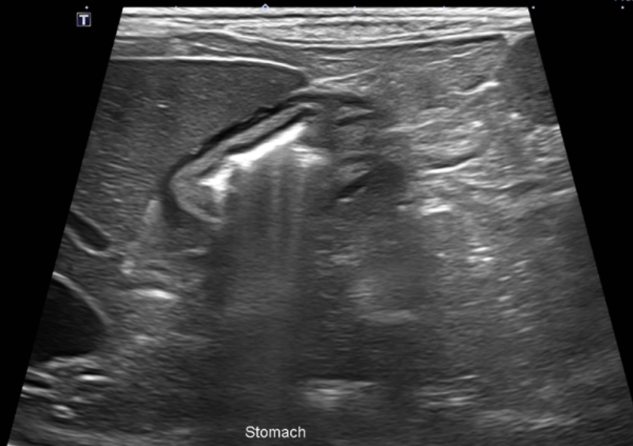

기본적인 혈액검사와 함께, 구토의 원인 중 소화기계 문제를 감별하기 위해 복부 초음파 검사를 진행하였습니다.

초음파 검사상에서는 특이 소견이 확인되지 않았습니다.